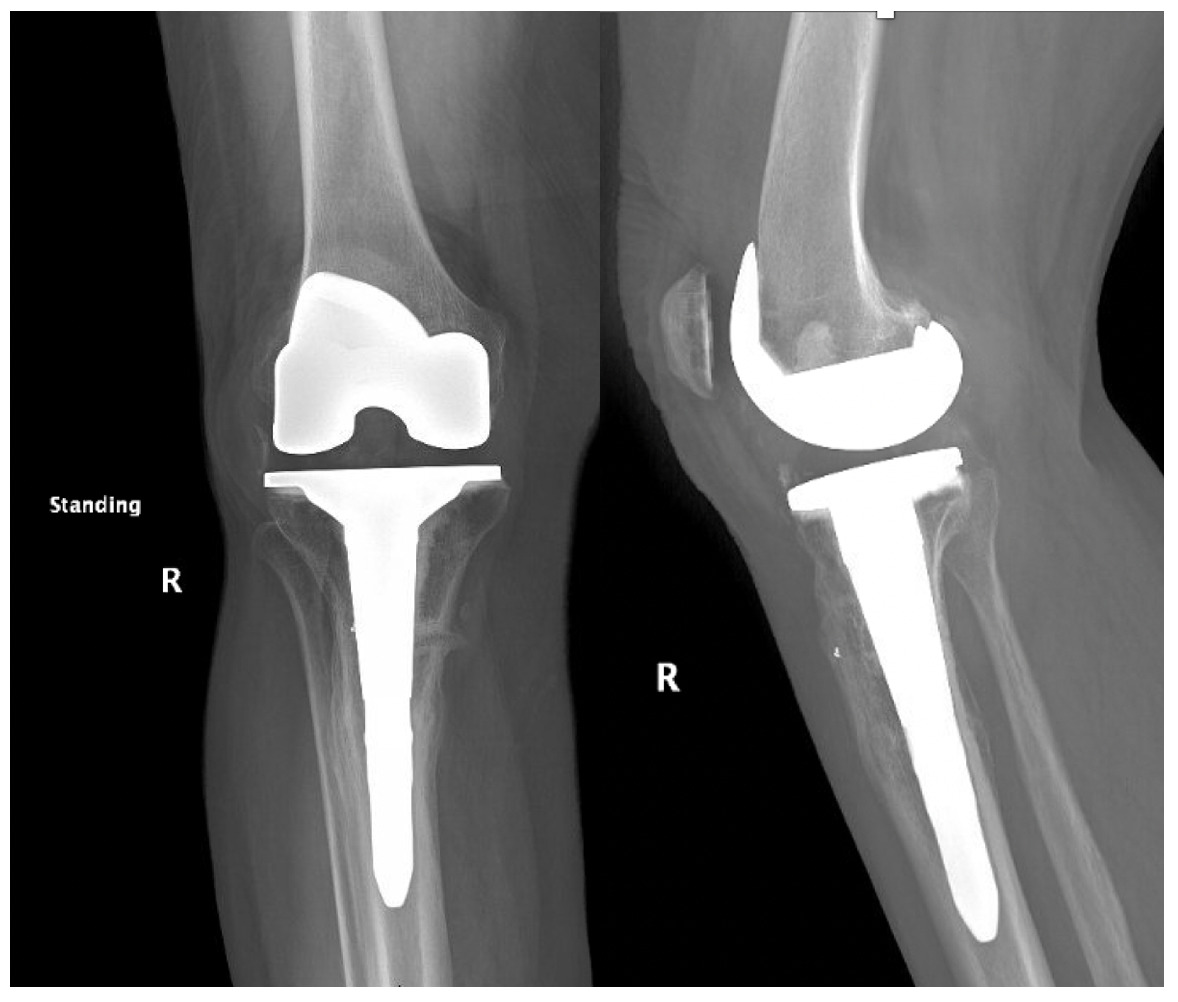

Trial components were inserted and demonstrated balanced flexion and extension gaps and central patellar tracking without the need for lateral release. The tibia was subsequently punched after confirming appropriate rotation for adequate patellar tracking. Final implantation proceeded with pressurized cement for the posterior-stabilized femoral component and the tibial baseplate under tourniquet insufflation. The diaphyseal press-fit stem was again confirmed to span the osteotomy by more than two cortical diameters under fluoroscopic guidance (Figure 4). Autogenous cancellous graft harvested from the femoral chamfer cuts was tightly packed into the osteotomy gap and along the medial cortex. The patella was resurfaced with a medialized polyethylene button.

The total estimated blood loss was 300 mL, and no transfusion was required. The patient tolerated oral intake on the evening of surgery, completed her first physiotherapy session the following morning, and ambulated fifty feet with a rolling walker while wearing the hinged knee brace locked in extension. Following ambulation, full length lower extremity films were re-obtained, demonstrating neutral mechanical hip–knee–ankle axis (Figure 5). She was discharged home on post-operative day two with acceptable pain control and an incision that was clean, dry, and intact.

Quantitative range-of-motion and outcome-score data are summarized in Table 1. At the two-week clinic visit the incision was fully healed and sutures were removed. The patient continued full weight bearing in the brace. By six weeks the osteotomy displayed bridging callus across the osteotomy site (Figure 6), the brace was discontinued, and she achieved an unrestricted gait pattern without assistive devices. Four months after surgery, the patient had resumed activities such as tennis and reported no pain or swelling. Radiographs at that time demonstrated complete cortical union without any interval changes in alignment (Figure 7). At the nine-month assessment she reported hiking up to five miles and skiing on groomed slopes without limitation. Imaging showed continued consolidation of the osteotomy and stable components (Figure 8).